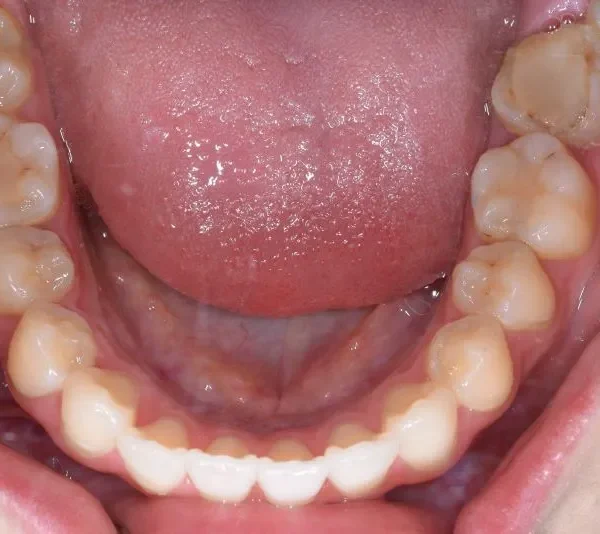

治療経過1

再治療の時は、上の歯は前から見えにくいオリジナル固定装置、下の歯はマルチブラケット装置を使用し、治療しました。

治療回数62回、1年6ヶ月の治療期間で矯正治療を終了しました。

前回の治療で歯の根っこの部分の位置を治していたので、全部前から付けるのではなく最低限見える装置で治せました。

一度治療して、後戻りでお困りの場合のご相談もお待ちしております。